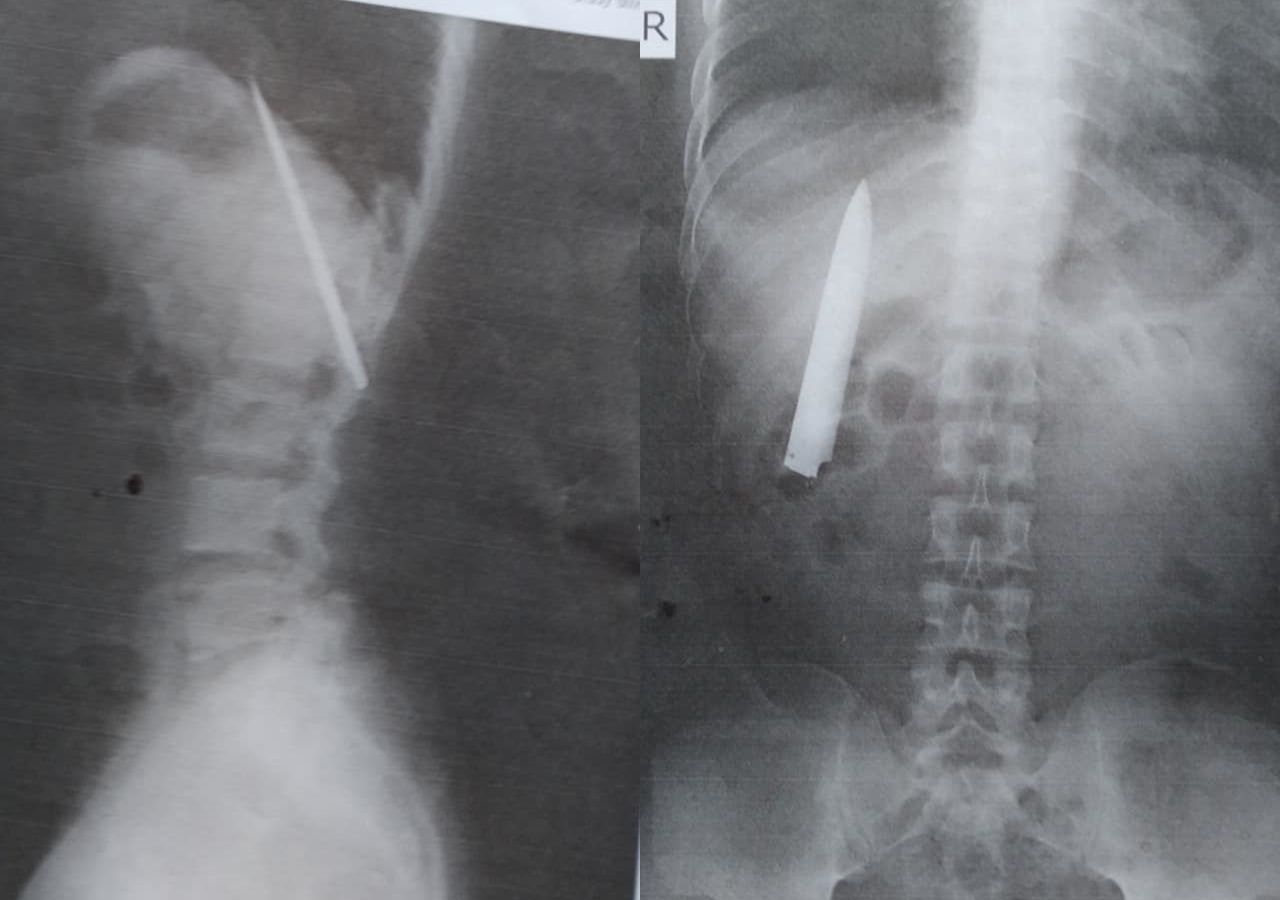

綜合外媒報導,一名25歲的菲律賓男子托莫(Kent Ryan Tomao)日前去面試一間採礦公司,公司要求他到醫院做X光檢查,卻意外發現他的胸口藏了一把約10公分長的刀子,且非常靠近肺部,情況相當危急,醫師判斷他必須立刻動手術取出這把刀。

托莫指出,他在去年1月時被數名少年持刀攻擊,當時被送往醫院治療,但該院醫護並沒有幫他做詳細檢查,僅告知他傷口很淺,縫合後便給他止痛藥讓他回家,直到現在才發現竟有刀子遺留在體內,讓他相當憤怒,「難怪我常在天氣冷的時候胸口痛」。